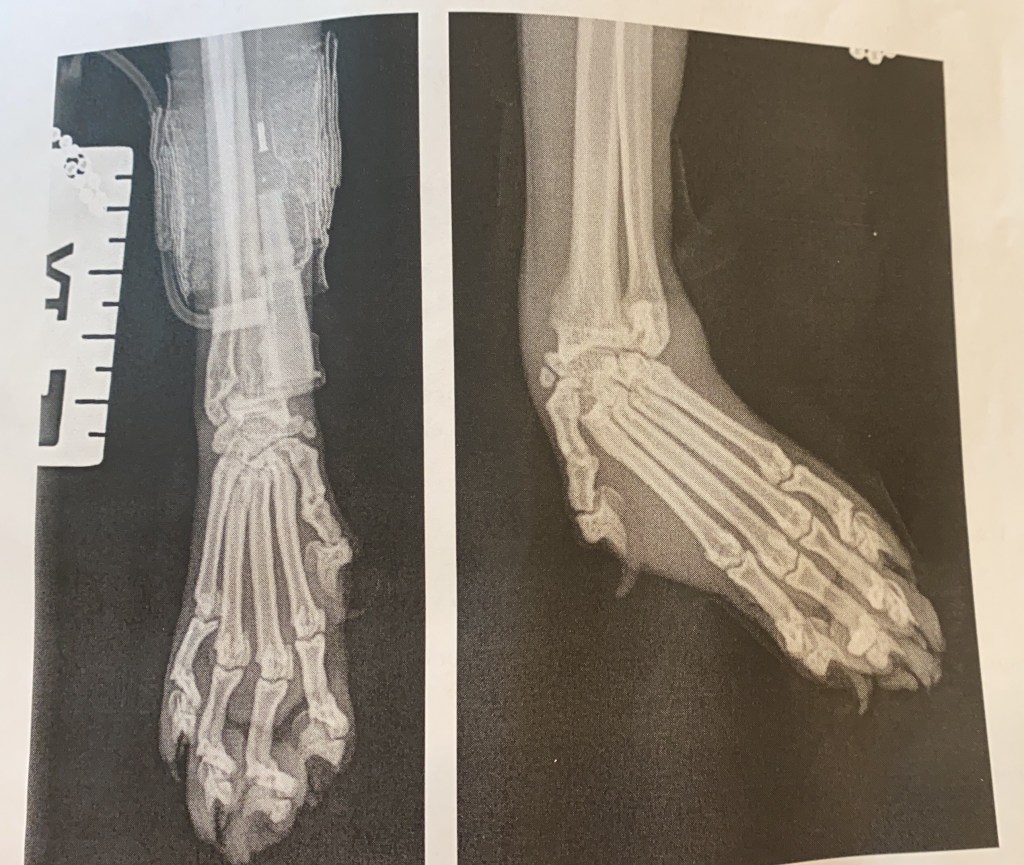

After a long sleepless night and anxious morning we got a call from the vet. The X-ray had showed that she had badly damaged her paw and ripped all the ligaments which is why her paw was at such a horrible angle. They described her injury as a catastrophic one and there was no doubt she would need surgery to repair it. They were concerned though as the x ray wasn’t detailed anough to show the state of the tiny bones in her ankle and paw so to get a better idea of how to fix her they needed to do a CT scan as well. We agreed. There were two options at this point:

It was a waiting game but there was nothing else we could do. Another sleepless night and long morning and then the call from the vet in the evening, they had the CT results and it showed that Millie hadn’t broken he bones in her paw or wrist but dislocated all of the wrist joints. The vets said they could fuse the joint and we didn’t need a further referral. This was the best outcome of the worst situation. We agreed to go ahead with the operation but there was a further complication, her paw was so swollen that they can’t operate yet, they wouldn’t be able to see the joints inside her paw well enough and the tissue wouldn’t be flexible enough to cover the wound properly so we must wait. In the meantime they had splinted it and bandaged it to help try to reduce the swelling.